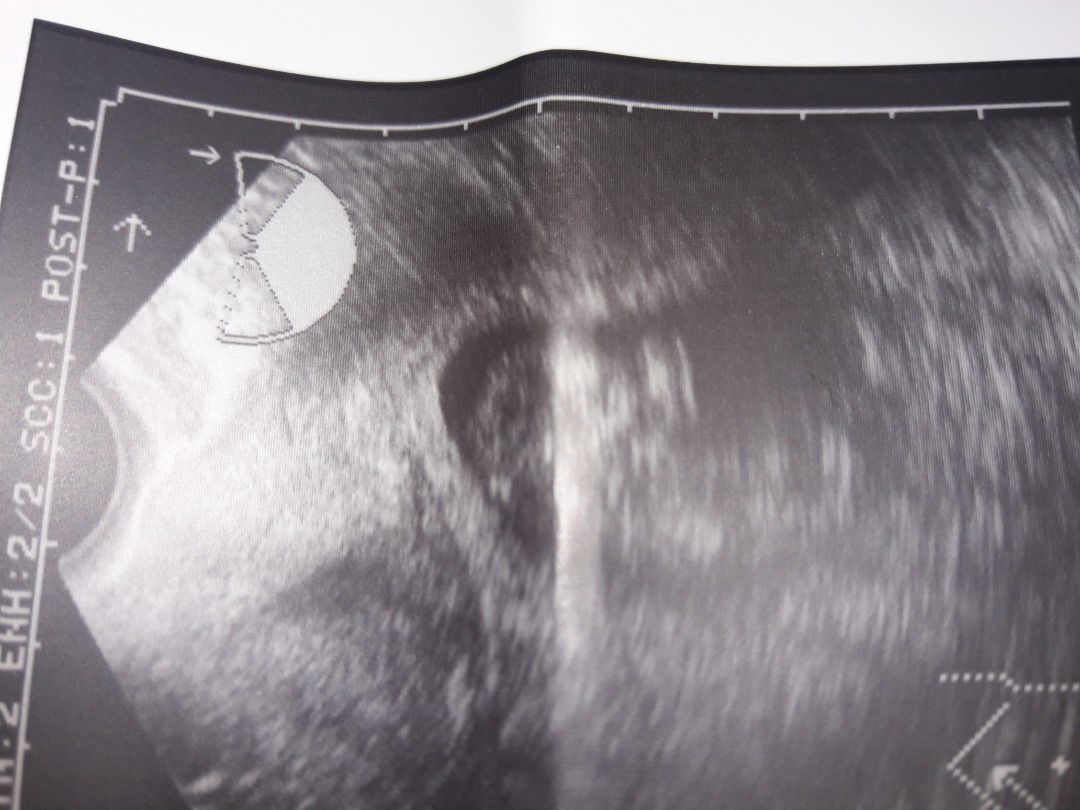

First TVS ko 3months preggy here...